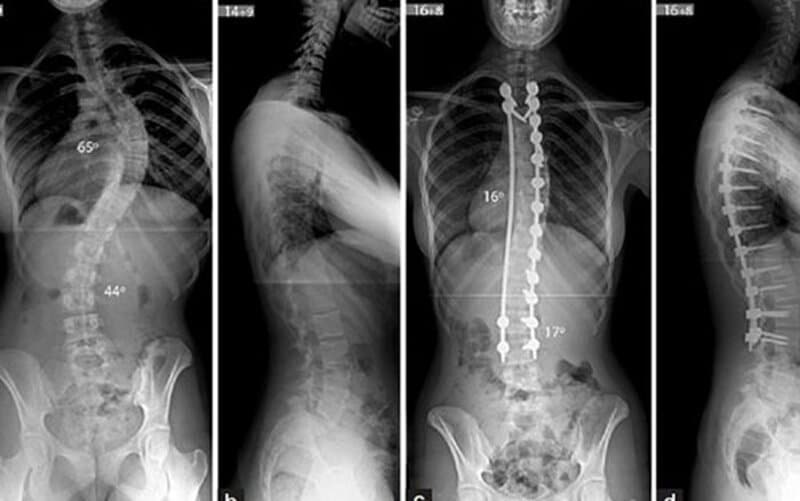

4.4. Đo và theo dõi cong vẹo cột sống ở trẻ em

– Xác định mức độ cong vẹo, góc lệch (góc Cobb)

– Hỗ trợ lập phác đồ điều trị hoặc can thiệp chỉnh hình